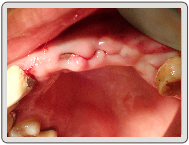

微創植牙-陳小姐

治療過程

缺牙狀況